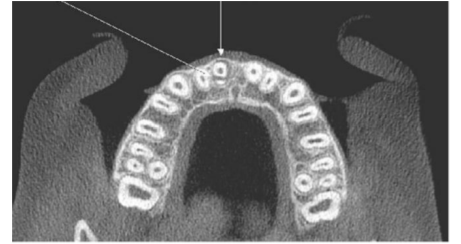

Identifique na radiografia o elemento dental fraturado: